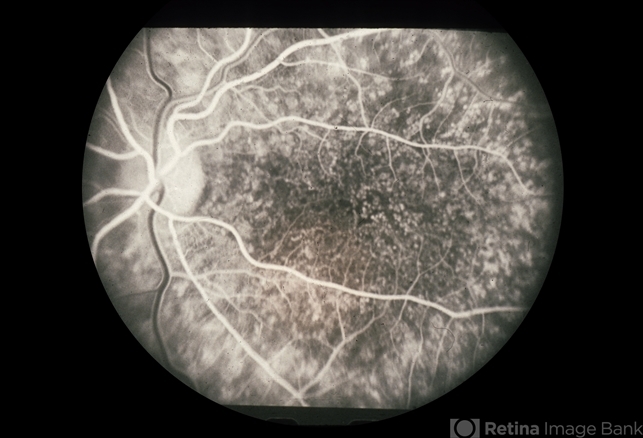

- cuticular drusen

- Cuticular drusen.